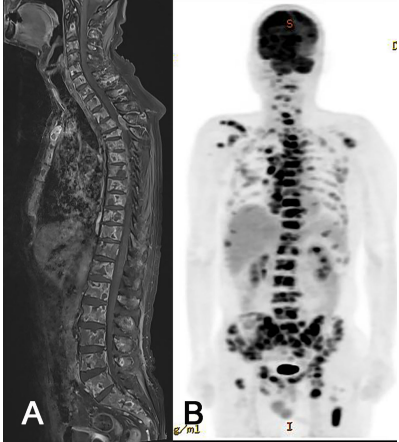

由于进行性肩部和背部疼痛,手术后9个月进行了包括脊柱MRI、正电子发射断层扫描(PET)-CT和胸部和腹部CT在内的系统评估,发现胸部和颈部淋巴结以及多个骨骼(包括椎骨、肩胛骨和骨盆)的广泛转移(图3)。对最大的脊椎损伤进行了活检,并诊断为转移性胶质母细胞瘤,胶质纤维酸性蛋白(GFAP)免疫阳性证明了这一点(图4)。尽管进行了脊柱放疗(24 Gy),但患者还是出现截瘫,接受了姑息治疗,并在手术后1年死亡。

图3. 神经外转移(ENM)的放射学图像。全脊柱MRI(A)和PET-CT(B)显示多个骨骼和淋巴结的广泛ENM